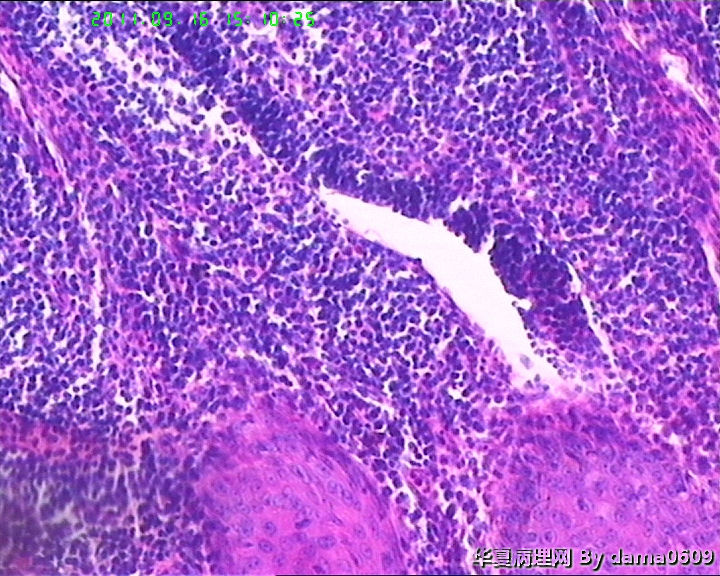

女,背部皮肤肿物,病史不详。送检梭皮组织一块,S:4.5x2.2cm,正中一圆形隆起,直径2.0cm,表面黄白色与周围界清,切面实性灰白色。

• 背部肿物,急请老师看看!!图2

图2

考虑T细胞淋巴瘤:依据1.淋巴样细胞浸润破坏性生长达肌组织;2.淋巴样细胞异型:核形不规则,大小不一,胞浆较丰富.注:表面上皮有增生需排除炎性反应.